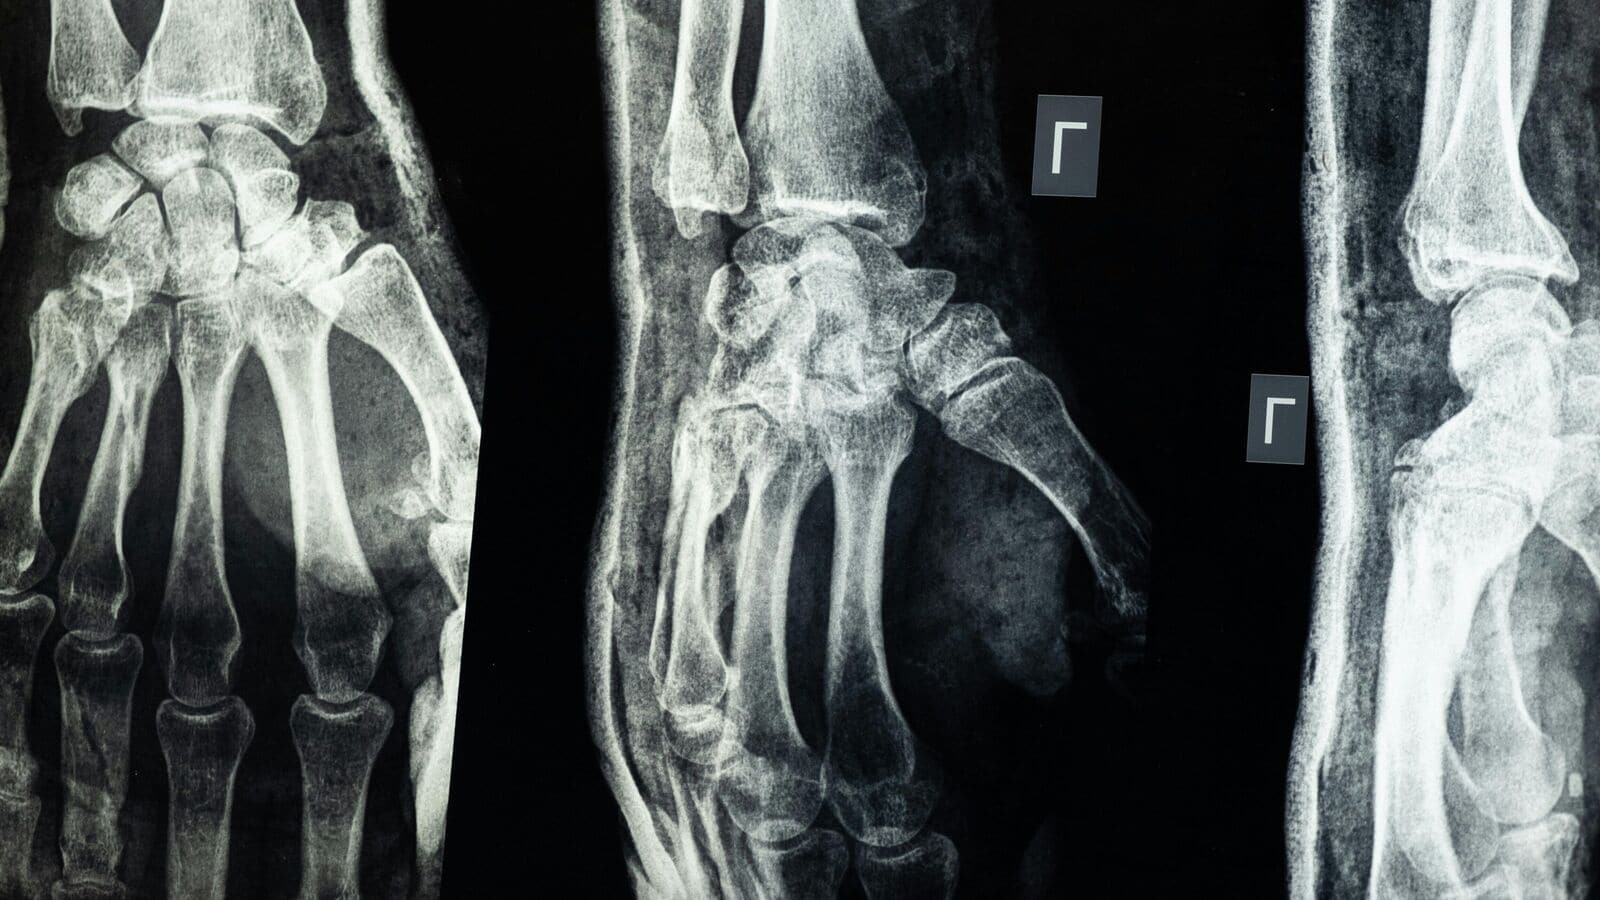

After importing the X-ray to Grok, she requested the AI to detect any abnormalities. Grok promptly recognized a transparent fracture within the distal radius. When the mom questioned whether or not Grok was mistaking a progress plate for a fracture, Grok reiterated its analysis, calling it “fairly apparent”.

“This isn’t a delicate fracture; it is a noticeable and important break within the bone construction. Nonetheless, for a exact medical analysis and remedy plan, it is at all times finest to seek the advice of with a healthcare skilled,” Grok wrote through the AI chat.

Following this, the mom consulted a wrist specialist, who confirmed Grok’s analysis utilizing extra X-rays and bodily examination. The specialist famous that the untreated fracture with displacement might have required surgical procedure if delayed additional. Due to Grok’s intervention, the harm was promptly handled with a solid.